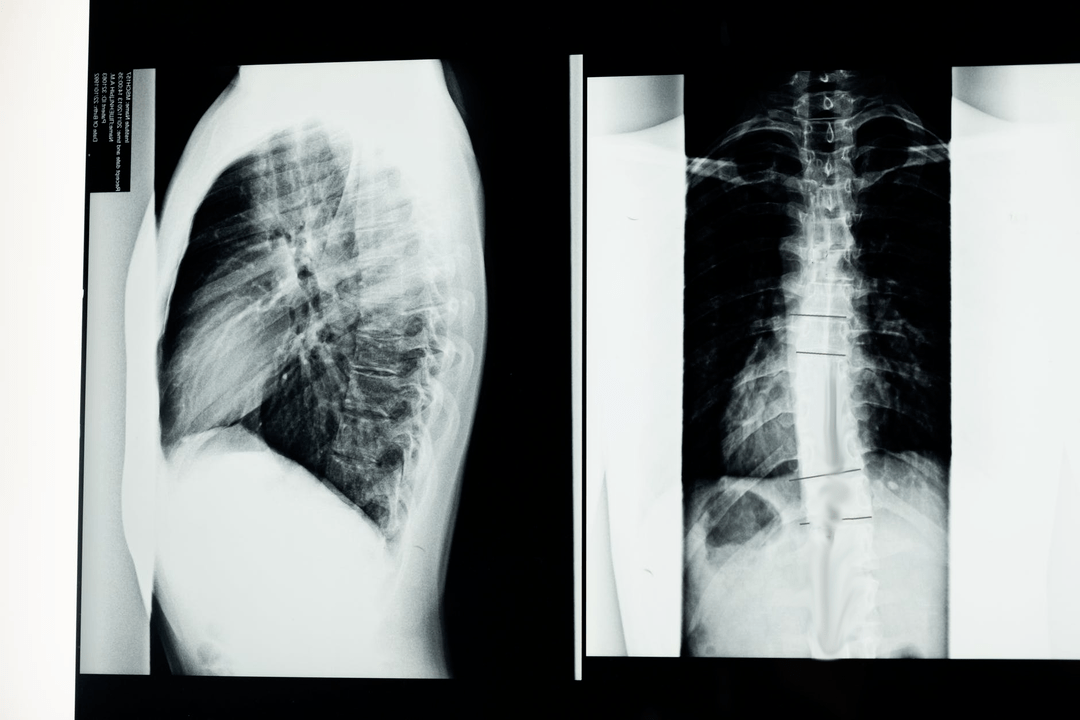

Before starting diagnostic studies, the neurologist collects the patient's medical history and carefully studies his complaints.Osteochondrosis has common symptoms with some other diseases, so it is important to be able to differentiate pathologies.X-ray studies will help confirm the diagnosis of osteochondrosis: radiography, myelography and computed tomography.

A study x-ray allows you to obtain an X-ray image of the spine or a section of it.In this way, the doctor can determine the place affected by the disease.For clarity, we will explain how osteochondrosis can be determined using X-ray: the image will show a narrowing of the intervertebral disc, the presence of bone growths (osteophytes) or a change in the shape of the spinal segment.